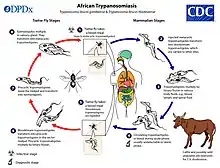

Human African trypanosomiasis

African trypanosomiasis is also known as African sleeping sickness. There are fewer than 10,000 cases currently.[39] Human African trypanosomiasis is vector-borne, and spread through the bite of the tsetse fly.[25] The most common symptoms are fever, headache, lymphadenopathy, nocturnal sleeping pattern, personality changes, cognitive decline, and coma. The disease is always fatal if untreated. The current forms of treatment are highly toxic and ineffective as resistance is spreading. It is diagnosed through an inexpensive serological test.